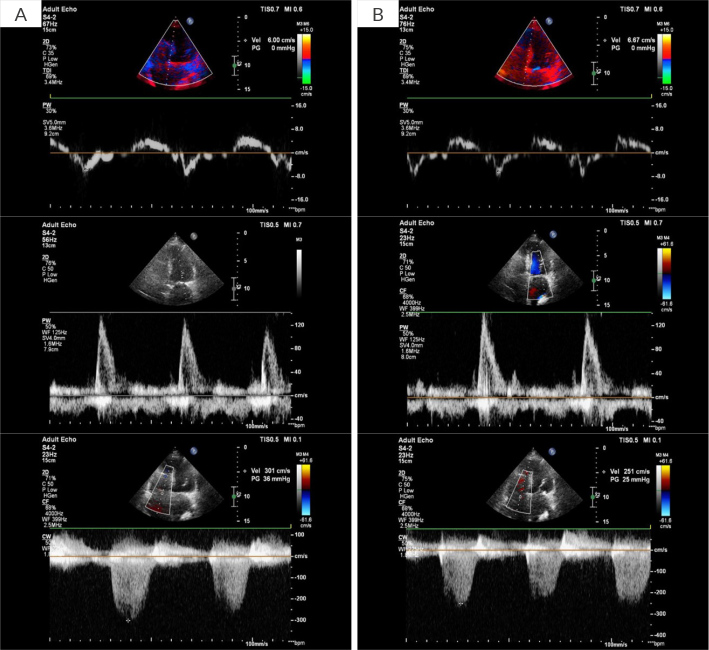

Case description: A 99-year-old female visited the clinic for a routine cardiac check-up. Laboratory investigations showed elevated NTproBNP and moderately elevated high sensitive troponin T. HeartCore algorithm indicated elevated LVFP. As part of the evaluation of worsening of sub-clinical HF, extended laboratory tests revealed low thyroid-stimulating hormone with high free thyroxine levels indicating increased thyroid function. The endocrinologist diagnosed hyperthyroidism with multinodular goitre and prescribed thiamazole. To prevent progression to clinical HF decompensation, the dose of furosemide was increased. At 4 months, during scheduled cardiac follow-up, the patient was clinically doing well, without any signs or symptoms of HF.

Learning points: Untreated thyroid disorders in patients with heart failure (HF) can exacerbate signs and symptoms of HF.Left ventricular filling pressure (LVFP) rises 3-4 weeks before HF symptoms. Echocardiographic assessment of LVFP can be challenging in patients with atrial fibrillation or paced rhythms.Photoplethysmography-based analysis could be utilized to assess LVFP, enabling remote monitoring of HF patients and potentially preventing HF decompensation and hospitalization.